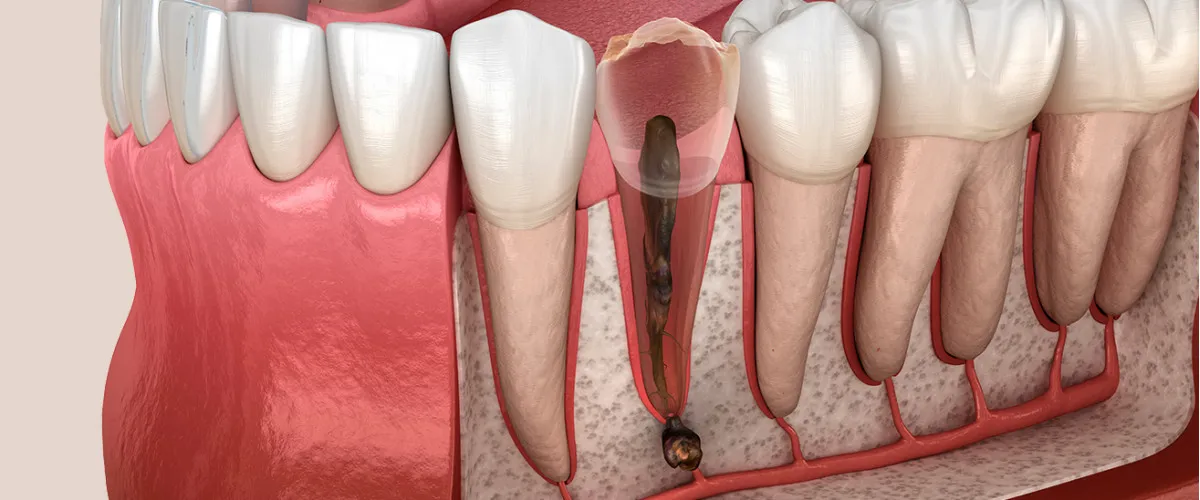

Viêm tủy răng là bệnh lý răng miệng nguy hiểm nếu không được điều trị kịp thời. Khi tủy răng bị viêm nhưng không được can thiệp, tình trạng viêm sẽ tiến triển thành xung huyết tủy. Do tủy răng được bao bọc bởi lớp thân răng cứng chắc, không có khả năng giãn nở, nên áp lực trong buồng tủy tăng cao, dẫn đến hoại tử và chết tủy.

Tủy răng chết không chỉ khiến răng mất đi sự sống mà còn là nguồn lây nhiễm vi khuẩn nghiêm trọng, có thể gây ra:

- Viêm chóp chân răng

- Áp xe quanh chóp

- Tiêu xương ổ răng

- Rụng răng sớm

- Viêm xương hàm và các biến chứng toàn thân nguy hiểm

🔹 Viêm tủy hoại tử

Đây là giai đoạn nặng nhất của viêm tủy răng, khi mô tủy đã bị chết hoàn toàn do nhiễm trùng kéo dài.

- Dịch nhiễm trùng từ ống tủy có thể lan qua chóp răng, gây viêm mô quanh chóp, áp-xe răng hoặc sưng đau vùng nướu.

- Viêm quanh chóp răng mạn tính, phá hủy xương ổ răng.

- Tiêu xương, tiêu chân răng, làm răng yếu dần.

- Mất răng và nguy cơ nhiễm trùng lan rộng sang các mô lân cận.